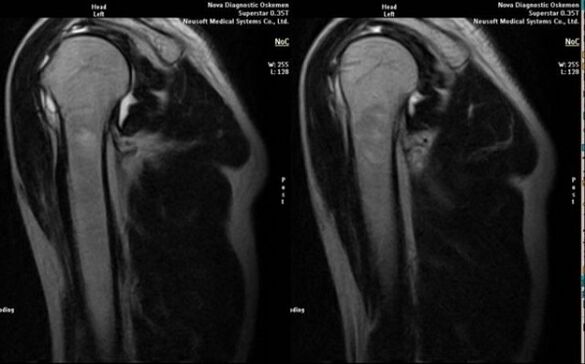

Principala metodă de diagnosticare pentru detectarea osteoartritei deformante a articulației umărului este radiografia simplă.

- rezonanță magnetică și tomografie computerizată;

Semnele care indică dezvoltarea artrozei includ în mod direct apariția unei îngustări semnificative a spațiului articular, scleroza structurilor subcartilaginoase, subțierea stratului de condrocite în sine, apariția osteofitelor și depunerea de cristale de sare în lichidul intraarticular.